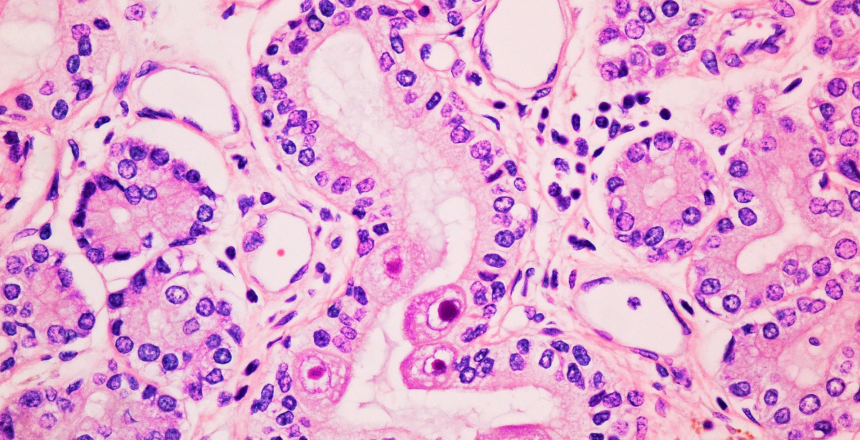

Фото - Цитомегаловирусная инфекция

Название вируса связано с его воздействием на клетки: пораженные клетки увеличиваются в размерах, образуя так называемые «цитомегалии».

• цитологические исследования – в моче или мазках могут обнаруживаться характерные увеличенные клетки с ядрами в виде «совиного глаза».